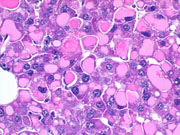

Hyaline bodies are occasionally seen in liver degeneration as well as in hepatocellular neoplasms of mice. In this example a large number of large hyaline bodies are concentrated in one region of the liver.